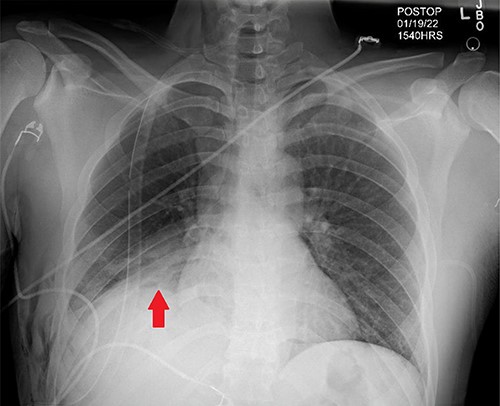

Days later, the patient was brought back to the operating theater for definitive repair of his diaphragmatic injury shown in Fig. 2A. Nonabsorbable sutures were utilized in a horizontal mattress technique to reapproximate the diaphragm thoracoscopically depicted in Fig. 2B and C, successfully reducing the liver into the abdomen. The phrenic nerve was identified and found to be intact prior to and after repair of the diaphragmatic injury. The patient tolerated the procedure well without complication. A postoperative chest X-ray (CXR) was done showing expansion of the right hemi-thorax compared with preoperative imaging as displayed in Fig. 3. On postoperative day (POD) #1, the patient’s thoracoscopic tube was taken off of suction and removed. His vital signs remained stable during his postoperative course with appropriate pain control; he was discharged home on POD#2.

Post-operative CXR demonstrating appropriate placement of a thoracoscopic tube and improvement of right-hemi-thorax eventration (Red arrow).